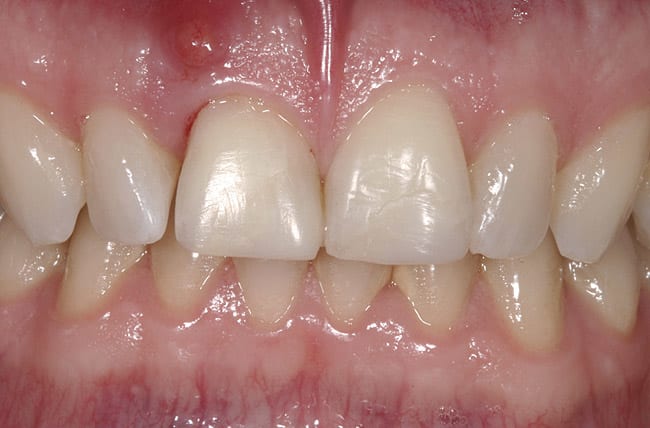

This case involved an ankylosed left central incisor. The patient’s chief complaint was that the incisor was dark and discolored (Figure 9 and Figure 10). Several possibilities were considered, including retaining the tooth or replacing it with an implant. The issue with retaining the incisor concerned the large pulpal canal and the need to aggressively prepare the tooth for a crown in order to mask the dark unesthetic dentin. Another concern was the long-term probability of external root resorption since it was ankylosed. The decision was made to extract and place an implant. The patient had good bone and good soft-tissue positions. The treatment plan was to extract and place the implant with an immediate protocol. The use of an immediate provisional was also considered, but the patient’s deep overbite and his desire to not have to be protective of the implant made the case for doing a bonded provisional. The incision design was done to allow for a facial flap but preserve the papilla. The extraction of the ankylosed incisor required magnification to dissect the tooth from the bone. The implant was placed and the site was grafted with hard and soft tissue. Figure 11 shows the implant, custom healing abutment, CTG, and closure with 7.0 vicryl sutures.

The final soft-tissue form was transferred with the impression by fabricating a custom impression coping, which was made with flowable composite and mimicked the cervical portion of the provisional restoration (Figure 12). The final restoration achieved the patient’s goal of matching the color and esthetic contours with the adjacent teeth. The gingival esthetics were ideal, making the implant undetectable from the natural dentition (Figure 13).